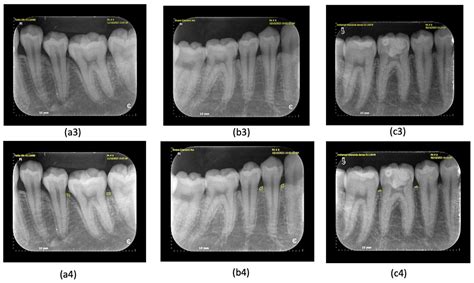

Medical professionals use multiple techniques to identify and diagnose these unique tumors:

• Imaging tests (X-rays, MRI, CT scans) • Blood tests to check hormone levels • Biopsy to determine malignancy